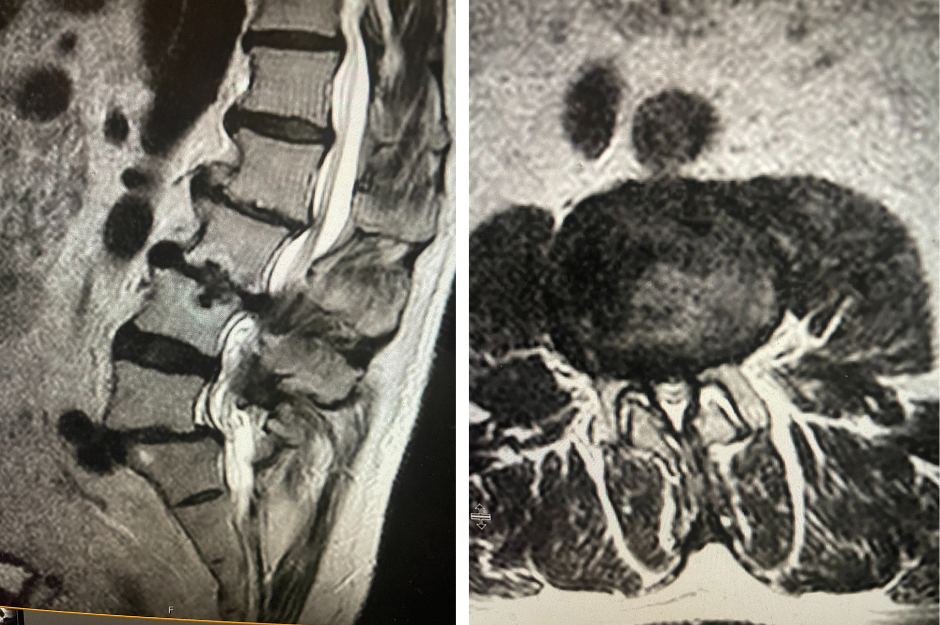

Figure 2. T2-weighted sagittal and axial MRIs demonstrating severe L3-4 stenosis and an L5-S1 grade 1 spondylolisthesis and spondylolysis and L3-4 retrolisthesis. Note the anterior osteophyte formation at L2-3 with attempted autostabilization of segment.

He had mild proximal weakness of his hip flexors. He also had a history of diabetes, hypertension, and hypercholesterolemia. Imaging studies were obtained. Plain x-rays (Fig. 1) demonstrated a degenerative levoscoliosis with the apex of the curve at L2-3. Lumbar MRI (Fig. 2) showed severe degenerative disc disease with an L5-S1 grade 1 spondylolisthesis and a significant retrolisthesis at L3-4 with severe lumbar stenosis.